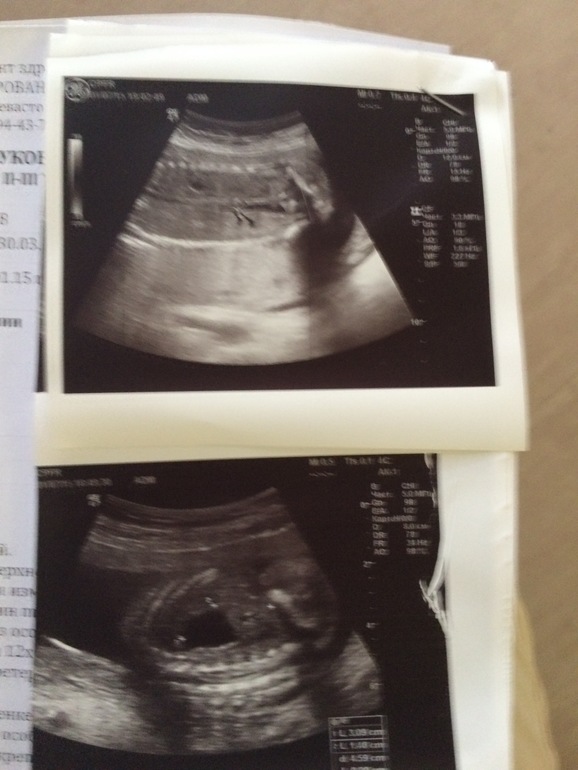

Добрый день. В 20 недель диагностировали на узи удвоение левой почки плода. Лоханка была расширена до 12мм.

в 22 недели было сделано экспертное УЗИ в ЦПСиР.

Там удвоения не нашли, но выдали более ужасное заключение.

прикрепляю результаты узи в ЦПСиР.